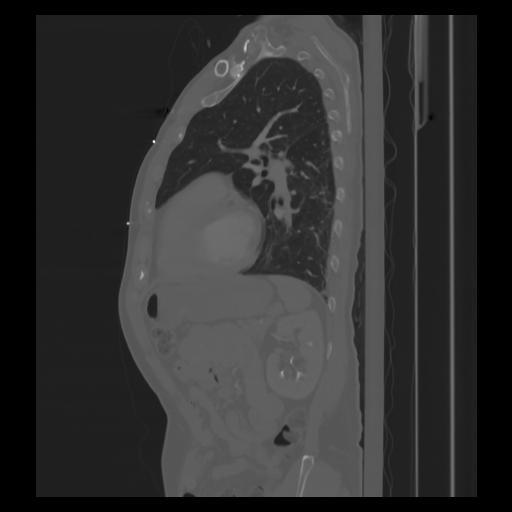

30 CUERPO,CE,Sagittal,3.000,CUERPO,Sagittal,